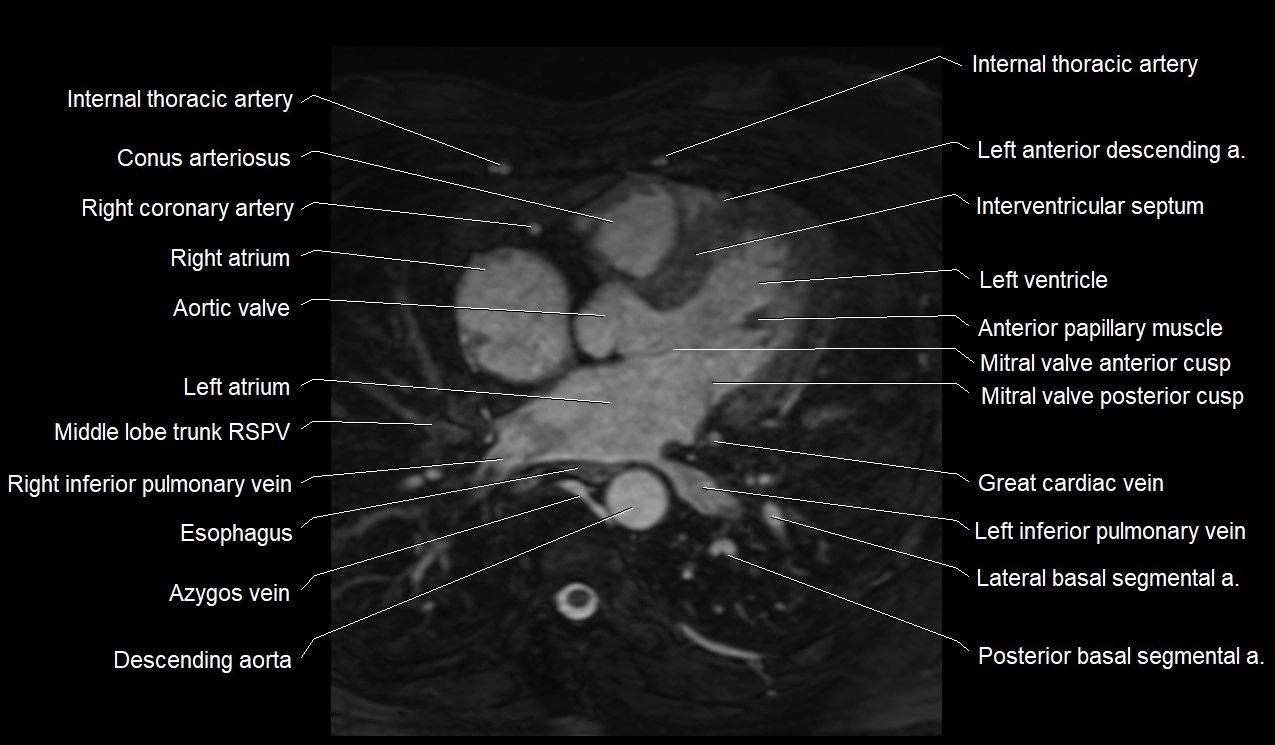

CT images